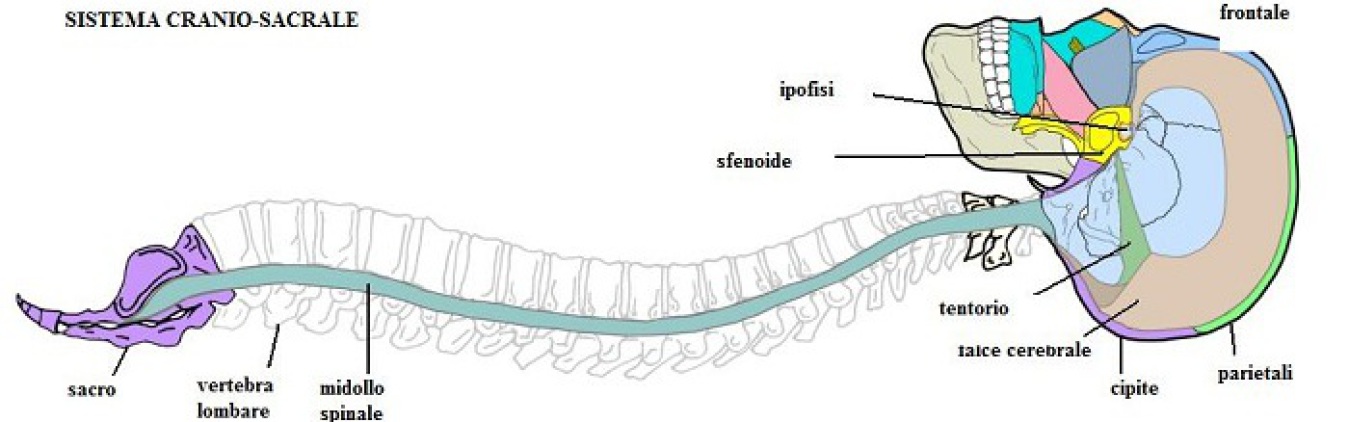

"Pensate di camminare alcune ore con un sassolino nella scarpa. Il sassolino è a contatto solo con il piede, ma vedrete che alla fine la postura sarà storta, vi sentirete doloranti e sarete di pessimo umore. Un muscolo contratto, un trauma, una cicatrice, una restrizione fasciale o un’emozione trattenuta possono dare lo stesso effetto globale."